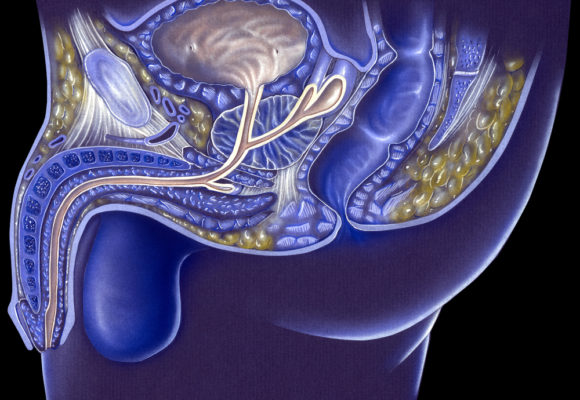

Laser Focal Therapy Effective, Causes Few Side Effects, 10-Year Trial Data Shows

Image-guided laser focal therapy is as effective as radical prostate removal surgery at treating men with localized prostate cancer, without the added risks of infection, incontinence, and erectile dysfunction, according to 10-year interim data from a Phase 2 trial. The trial findings were slated to be presented in a poster, “Outpatient Trans-Rectal MR-Guided Laser Focal…

University of Colorado Launches PreView Medical for PC Diagnosis, Treatment

The University of Colorado Anschutz Medical Campus, led by CU Innovations, has partnered with medical technology entrepreneurs Jonathan Gasson and Sharon Lake to form a new company called PreView Medical, which will focus on the development and optimization of new diagnostic procedures and treatments for prostate cancer. PreView Medical’s ClariCore System is based on a…

Vaccine Shows Promise in Advanced Prostate Cancer, Proof-of-Concept Study Shows

YourVaccx, a new type of cancer vaccine developed by ImmunSYS, is safe and shows promising effectiveness in patients with metastatic prostate cancer and other difficult-to-treat advanced solid tumors, a proof-of-concept study shows. Study findings were presented in a poster titled, “Regression of metastatic cancer and abscopal effects following in situ vaccination by cryosurgical tumor cell…